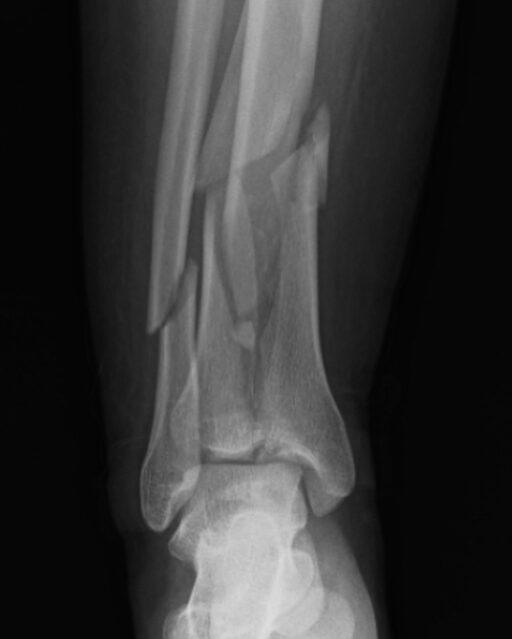

Manejo inicial en las fracturas complejas de tibia

El manejo inicial de una fractura compleja de tibia representa un punto de inflexión en el proceso de recuperación del paciente. Tal como lo destacó el Dr. Escobar, la fijación